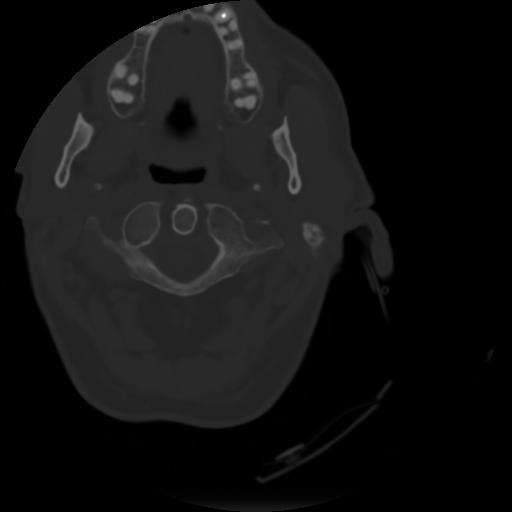

3 CEREBRO,,Axial,3.0,CEREBRO,,